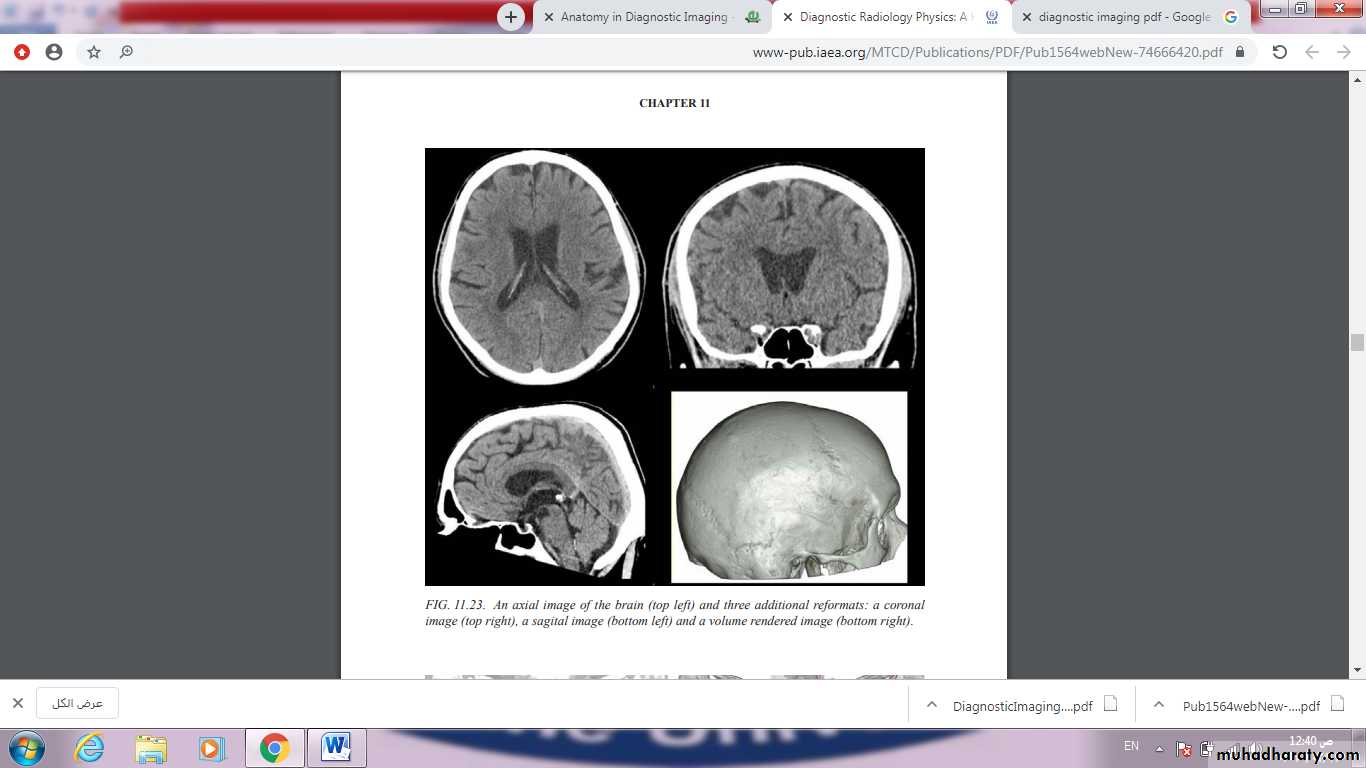

A computerized tomography (CT) scan combines a series of X-ray images taken from different angles around your body and uses computer processing to create cross-sectional images (slices) of the bones, blood vessels and soft tissues inside your body. CT scan images provide more-detailed information than plain X-rays do.

A CT scan or computed tomography scan makes use of computer-processed combinations of many X-ray measurements taken from different angles to produce cross-sectional images of specific areas of a scanned object, allowing the user to see inside the object without cutting.